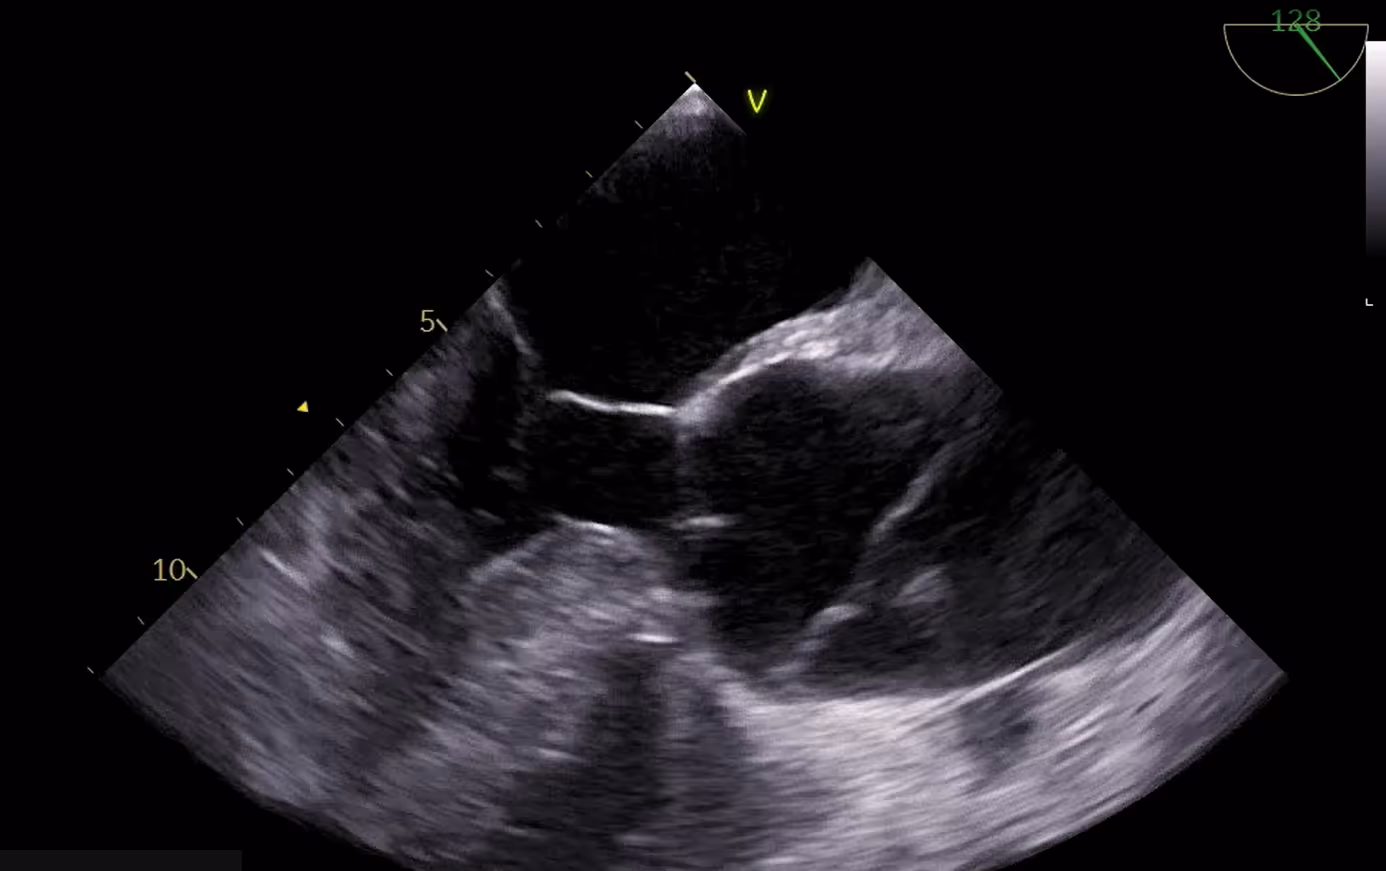

Takotsubo cardiomyopathy with left ventricular outflow tract obstruction...

2021-02-02

in

Clinical Cases